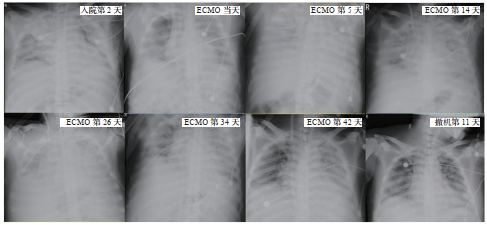

1.4 诊治经过及临床转归入院诊断:⑴多发伤, ①腹部闭合伤, 剖腹探查、脾破裂切除术后,小肠、膀胱、腹壁、肠系膜及胰腺损伤修补术后,胰瘘;②双侧多发肋骨骨折,肺挫伤,气胸,纵隔气肿;③腰1~5右侧横突骨折,腰2左侧横突骨折。⑵肺炎,急性呼吸衰竭。患者入院后予镇静镇痛、呼吸机支持、注射用亚胺培南西司他丁钠1.0 g静滴1次/8 h抗感染、肠内营养、预防深静脉血栓等支持治疗。入院后患者呼吸功能持续恶化,第7天氧合指数低至56.5 mmHg,考虑ARDS,于2019年11月5日紧急行VV-ECMO治疗(Cardiohelp®,德国MAQUET公司)。ECMO治疗期间采取严格的综合性感染防治措施,同时通过监测病原学和炎症指标(CRP、PCT、IL-6等)调整抗感染策略,未发生严重感染。抗凝采用肝素钠注射液,维持目标激活全血凝固时间(ACT)160~200 s,治疗后期肝素用量明显增大(1 000 U/h)且ACT仍未达标,于12月16日改用比伐芦定抗凝,患者12月17日凝血功能提示凝血酶时间(TT)显著延长(128.4 s),同时出现解黑便1次,大便隐血3+,血红蛋白(Hb)从90 g/L降至83 g/L,及时降低抗凝强度,调整ACT目标160~180 s,并输注悬浮红细胞2 U,消化道出血好转。此外,采用严格容量管理策略,相对低热[(25 kcal/(kg·d)]幽门后喂养,以及综合辅助治疗(包括翻身、背部振动排痰等胸部物理治疗和早期康复措施),ECMO治疗历时46 d,期间4次(11月21日、12月3日、12月10日和12月16日)更换膜肺,患者肺部功能终获好转,于2019年12月21日顺利撤除ECMO,后继续呼吸机支持治疗,2020年01月11日停呼吸机改面罩吸氧。2020年1月15日转入普通病房,1月22日拔除气切套管,1月24日顺利出院。治疗过程中患者胸部影像变化趋势详见图 1。

| 图 1 床旁胸部X线变化 |